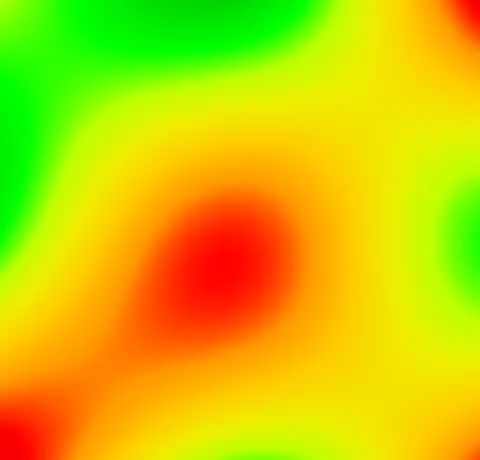

imp2field -like out.mnc out.imp field.mnc

And then produce an image of it using the Spectral colormap

mincpik -scale 2 field.mnc -slice 150 -lookup -spectral field.png